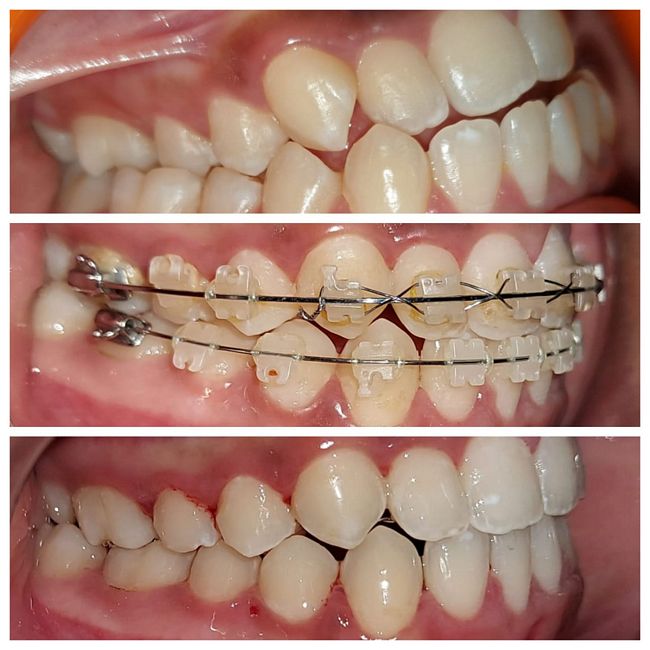

Inta-oral : Pre, Mid & Post-treatment : Right Lateral View

Intra-oral : Pre, Mid & Post-treatment : Left Lateral View